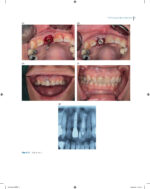

Immediate Dental Implants for Esthetic and Premolar Sites 2025

کتاب افست “Immediate Dental Implants for Esthetic and Premolar Sites 2025” ویرایش اول